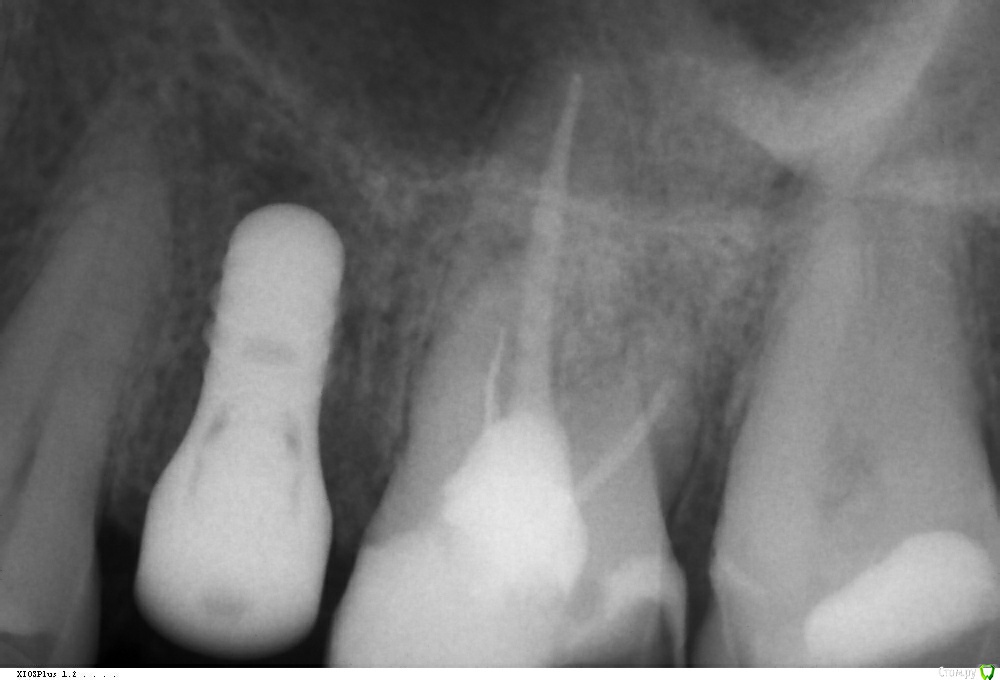

Amigo43 Опубликовано 3 сентября, 2019 Поделиться Опубликовано 3 сентября, 2019 Правильно ли я понимаю, что это штрауманн тл утопленный полированной шейкой в кость? Ссылка на комментарий

Dmitry DK Опубликовано 3 сентября, 2019 Автор Поделиться Опубликовано 3 сентября, 2019 Правильно ли я понимаю, что это штрауманн тл утопленный полированной шейкой в кость?да, это он Ссылка на комментарий

Dmitry DK Опубликовано 4 сентября, 2019 Автор Поделиться Опубликовано 4 сентября, 2019 так нужно было его просто глубже поставитьБыли такие мысли)Имплантат упёрся в нижнюю стенку синус. Весь винт с полированной частью 9,8 мм, шероховатая часть - 8 мм, от небной стеньки до синуса - 8 мм. Выбор был 1) закрытый синус, глубже платформа 2) выше платформа, без синусаВторой вариант выбран только по причине низких эстетических требований пациентки. 1 Ссылка на комментарий